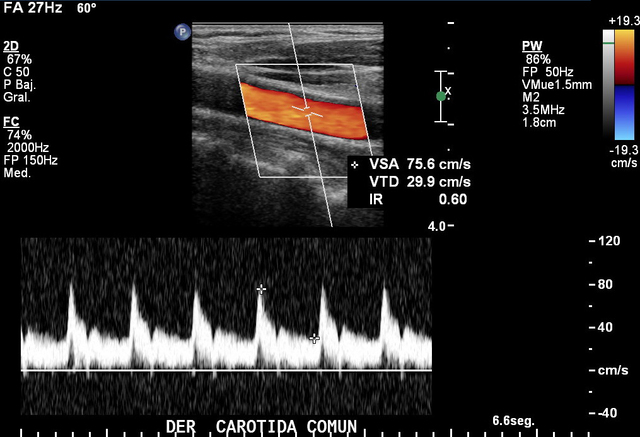

• El Doppler

El Doppler

En 1964 apareció la técnica Doppler para estudiar las carótidas, con gran aplicación en Neurología.